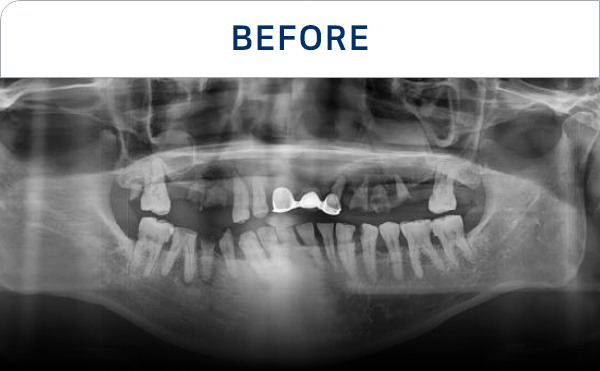

전후가 명확한 결과, 그 결과가

곧 신길플란트치과의 신뢰입니다.

불편함 없이 웃고, 걱정 없이 드실 수 있도록 임플란트로 일상의 편안함을 되찾아드리겠습니다.